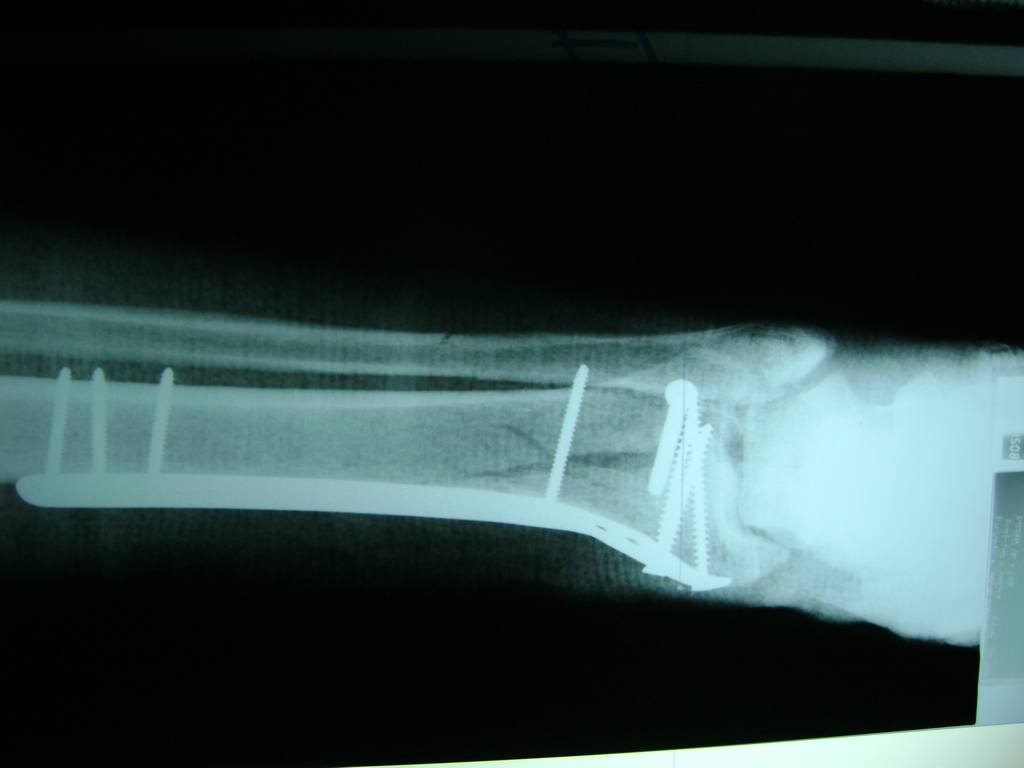

La mayor parte de las roturas implican a la parte proximal del hueso (parte del hueso próximo a la rodilla) o a la parte distal (parte del hueso cerca del tobillo).